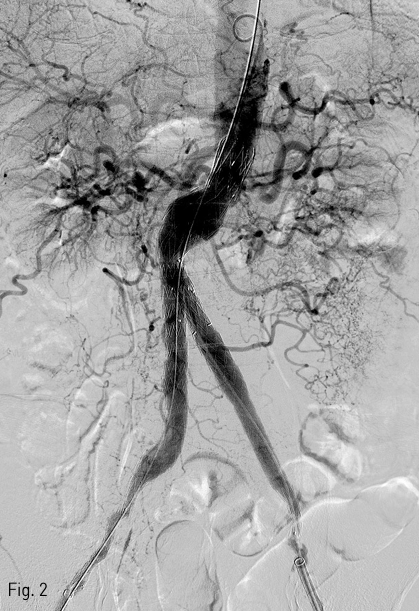

Fig 2

Post EVAR angiography reveals successful exclusion of aortic aneurysm.

2018년 좌측발의 통증과 색깔변화를 주소로 내원하여 시행한 조영증강 CT(Fig. 1)상에서 발견된 복부대동맥 및 양측 장골 동맥류에 대해 InCraft(Cordis, Milpats, US)를 이용한 EVAR 치료(Fig. 2)를 받은 환자로, 술후 퇴원전 조영증강 CT(Fig. 3)상에서 우측 장골 분지 인조혈관이 폐색된 소견을 보였다.